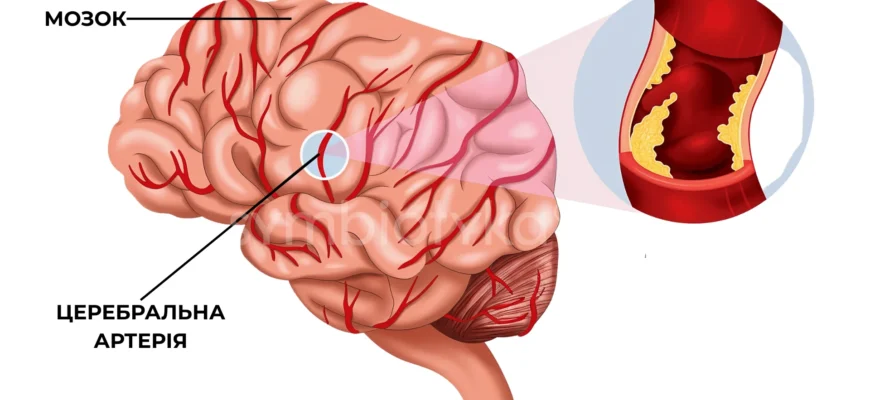

Загальні факти про цереброваскулярні хвороби

Так, розпочнемо з того, що ці хвороби можна порівняти з піснею, яка розриває радіо: вони в списку лідерів серед причин смерті та інвалідності у світі. Щороку мільйони людей стають жертвами цереброваскулярних проблем… Чому? Усього один рядок: порушення кровопостачання мозку. Ах, от так просто? Не зовсім.

- Інсульти – найбільш серйозні. Найнебезпечніші та неочікуваніше. Класика жанру: ішемічний та геморагічний.

- Ішемічна хвороба мозку. Всі ці постійні мігрені. Чи-то нестерпні головні болі? Хтозна, це воно – всі оті неприємності.

- Транзиторні ішемічні атаки. Миготіння? Спалахи? Це обмани вашого свідомості… з ними варто бути насторожі.

Інсульт: невидимий рядок у мелодії

Якщо задуматись, інсульт – це наче неприємний сюрприз. Ніби вимкнули улюблену мелодію на середині. все зупиняється, життя ламається навпіл. Люди, котрі його пережили, знають: нічого не можна передбачити.